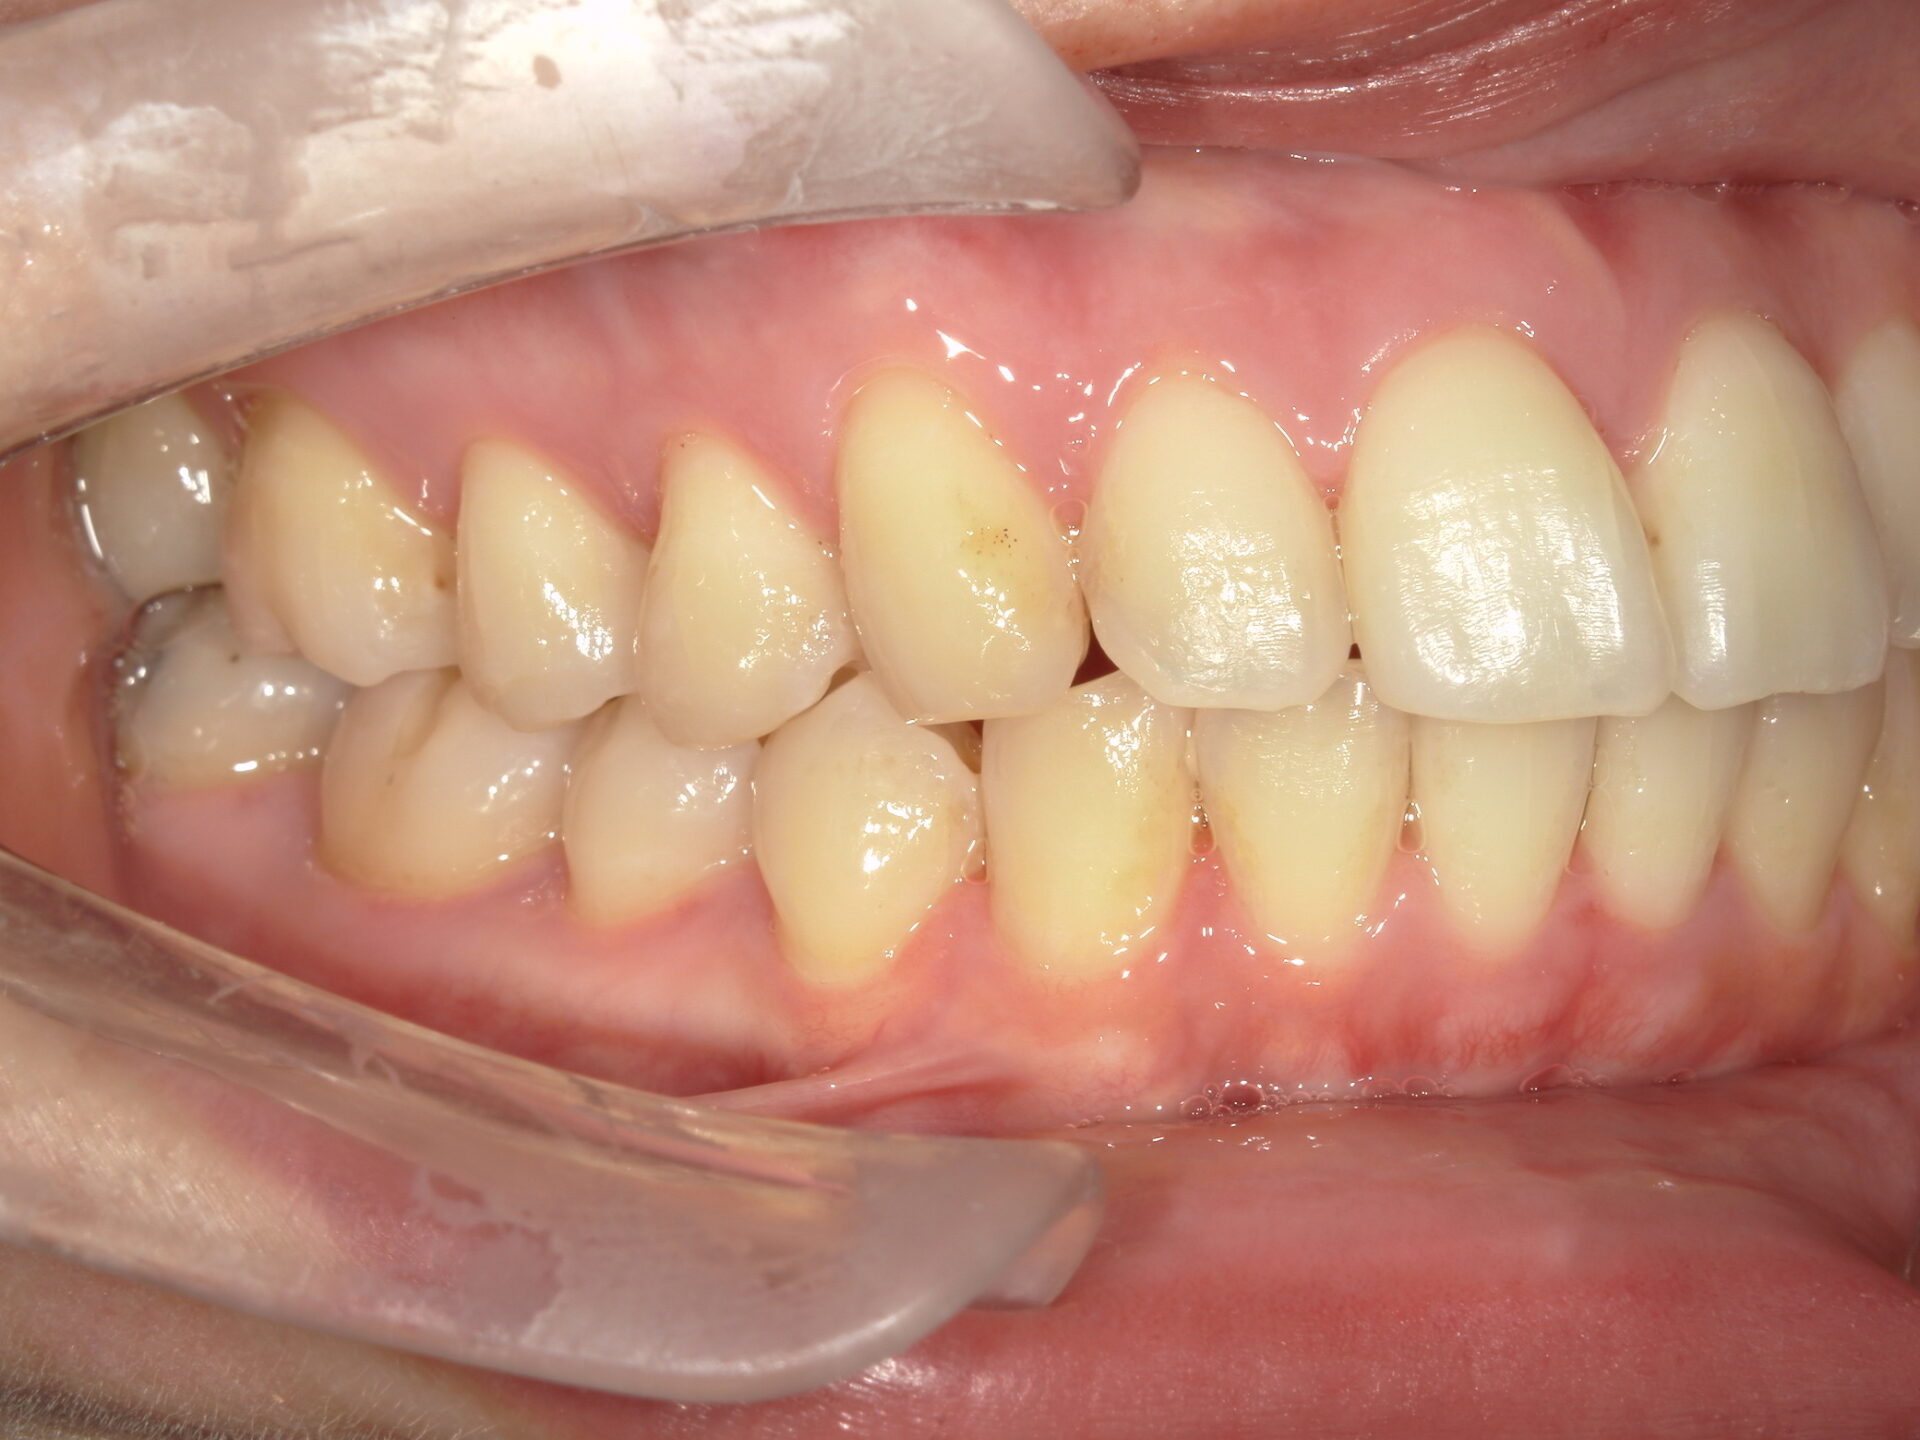

before

患者さんの年齢 30代 女性 症状 見た目がコンプレックス 治療内容 マウスピース矯正治療(抜歯あり) 費用 90万(税抜) 治療期間・回数 治療期間2年、通院回数10回 デメリット・リスク 期間がかかることがある 患者さまの声 なんでも噛める。本当に治療して良かった。 - 矯正治療